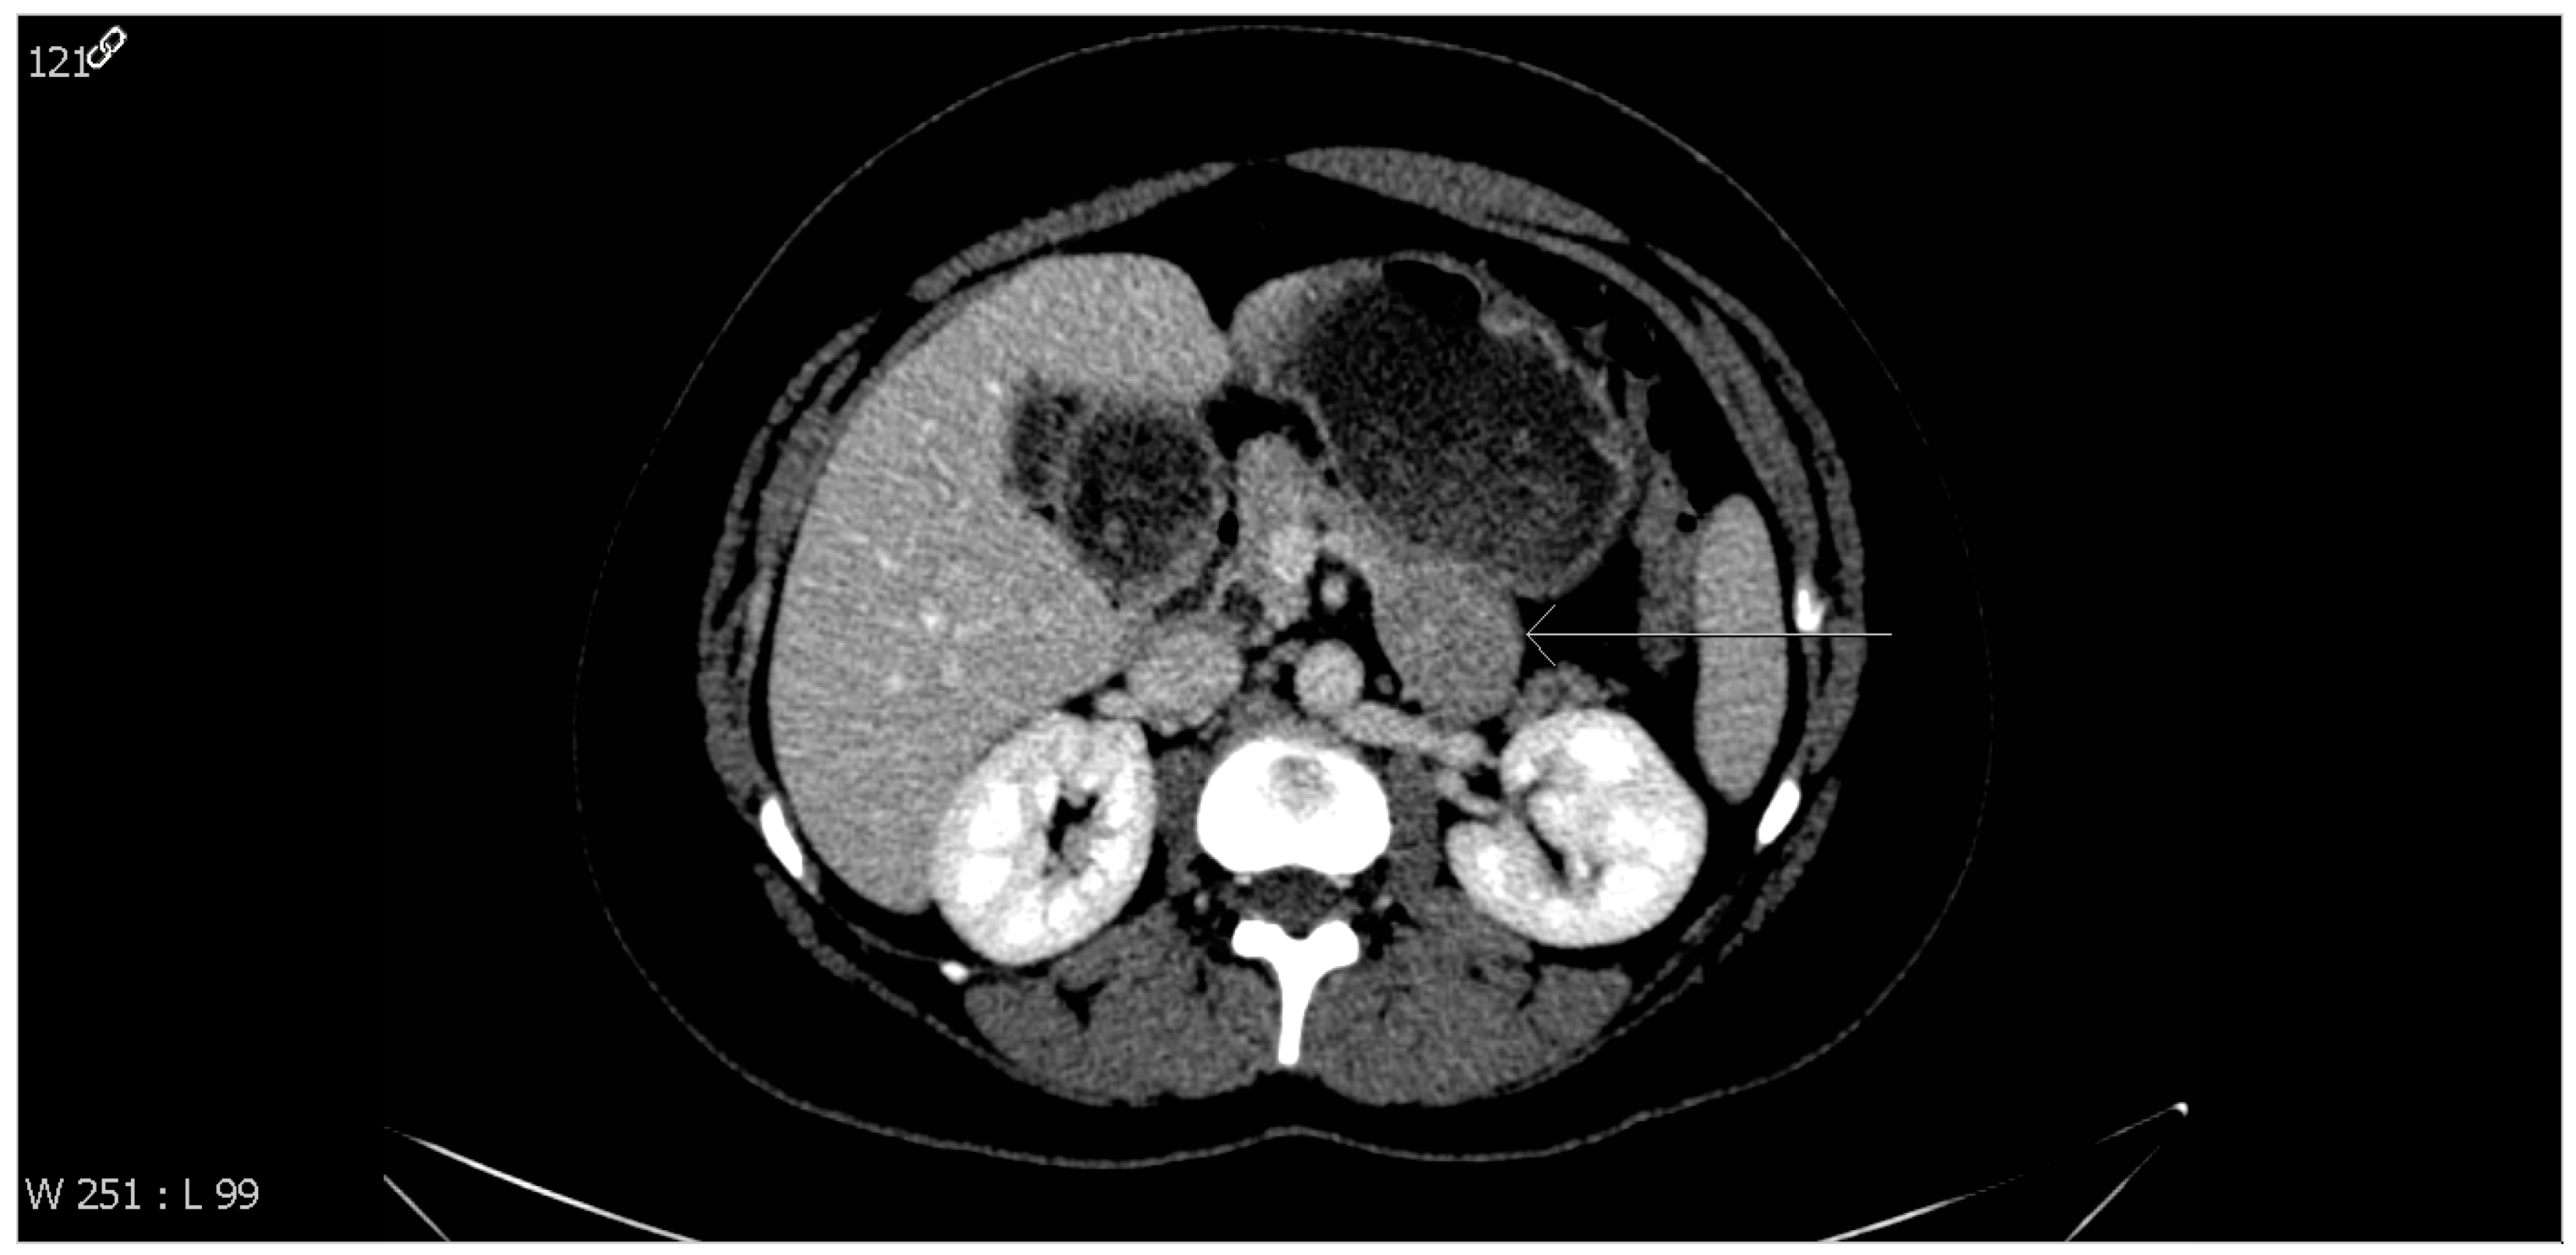

2. Case Report

2.1. Clinical History

2.2. Pathological Findings